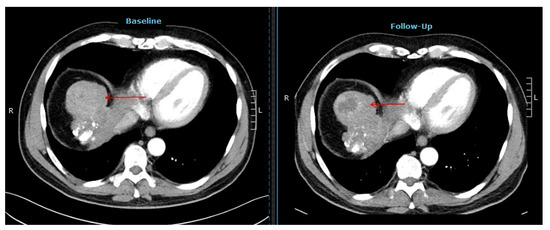

2.2. Response and Survival